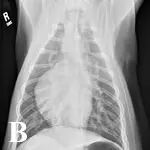

Thoracic radiography and abdominal ultrasonography were performed to screen for an inciting cause of MG. Thoracic radiographs (Figure 1) showed a well-circumscribed, spherical-to-ovoid cranial mediastinal mass and moderate megaesophagus. Thymoma was considered the most likely cause. There was no evidence of aspiration pneumonia. Abdominal ultrasonography was unremarkable.

Figure 1. Lateral (A) and ventrodorsal (B) thoracic radiographs showing a round, circumscribed mass in the cranial thorax and moderate megaesophagus.